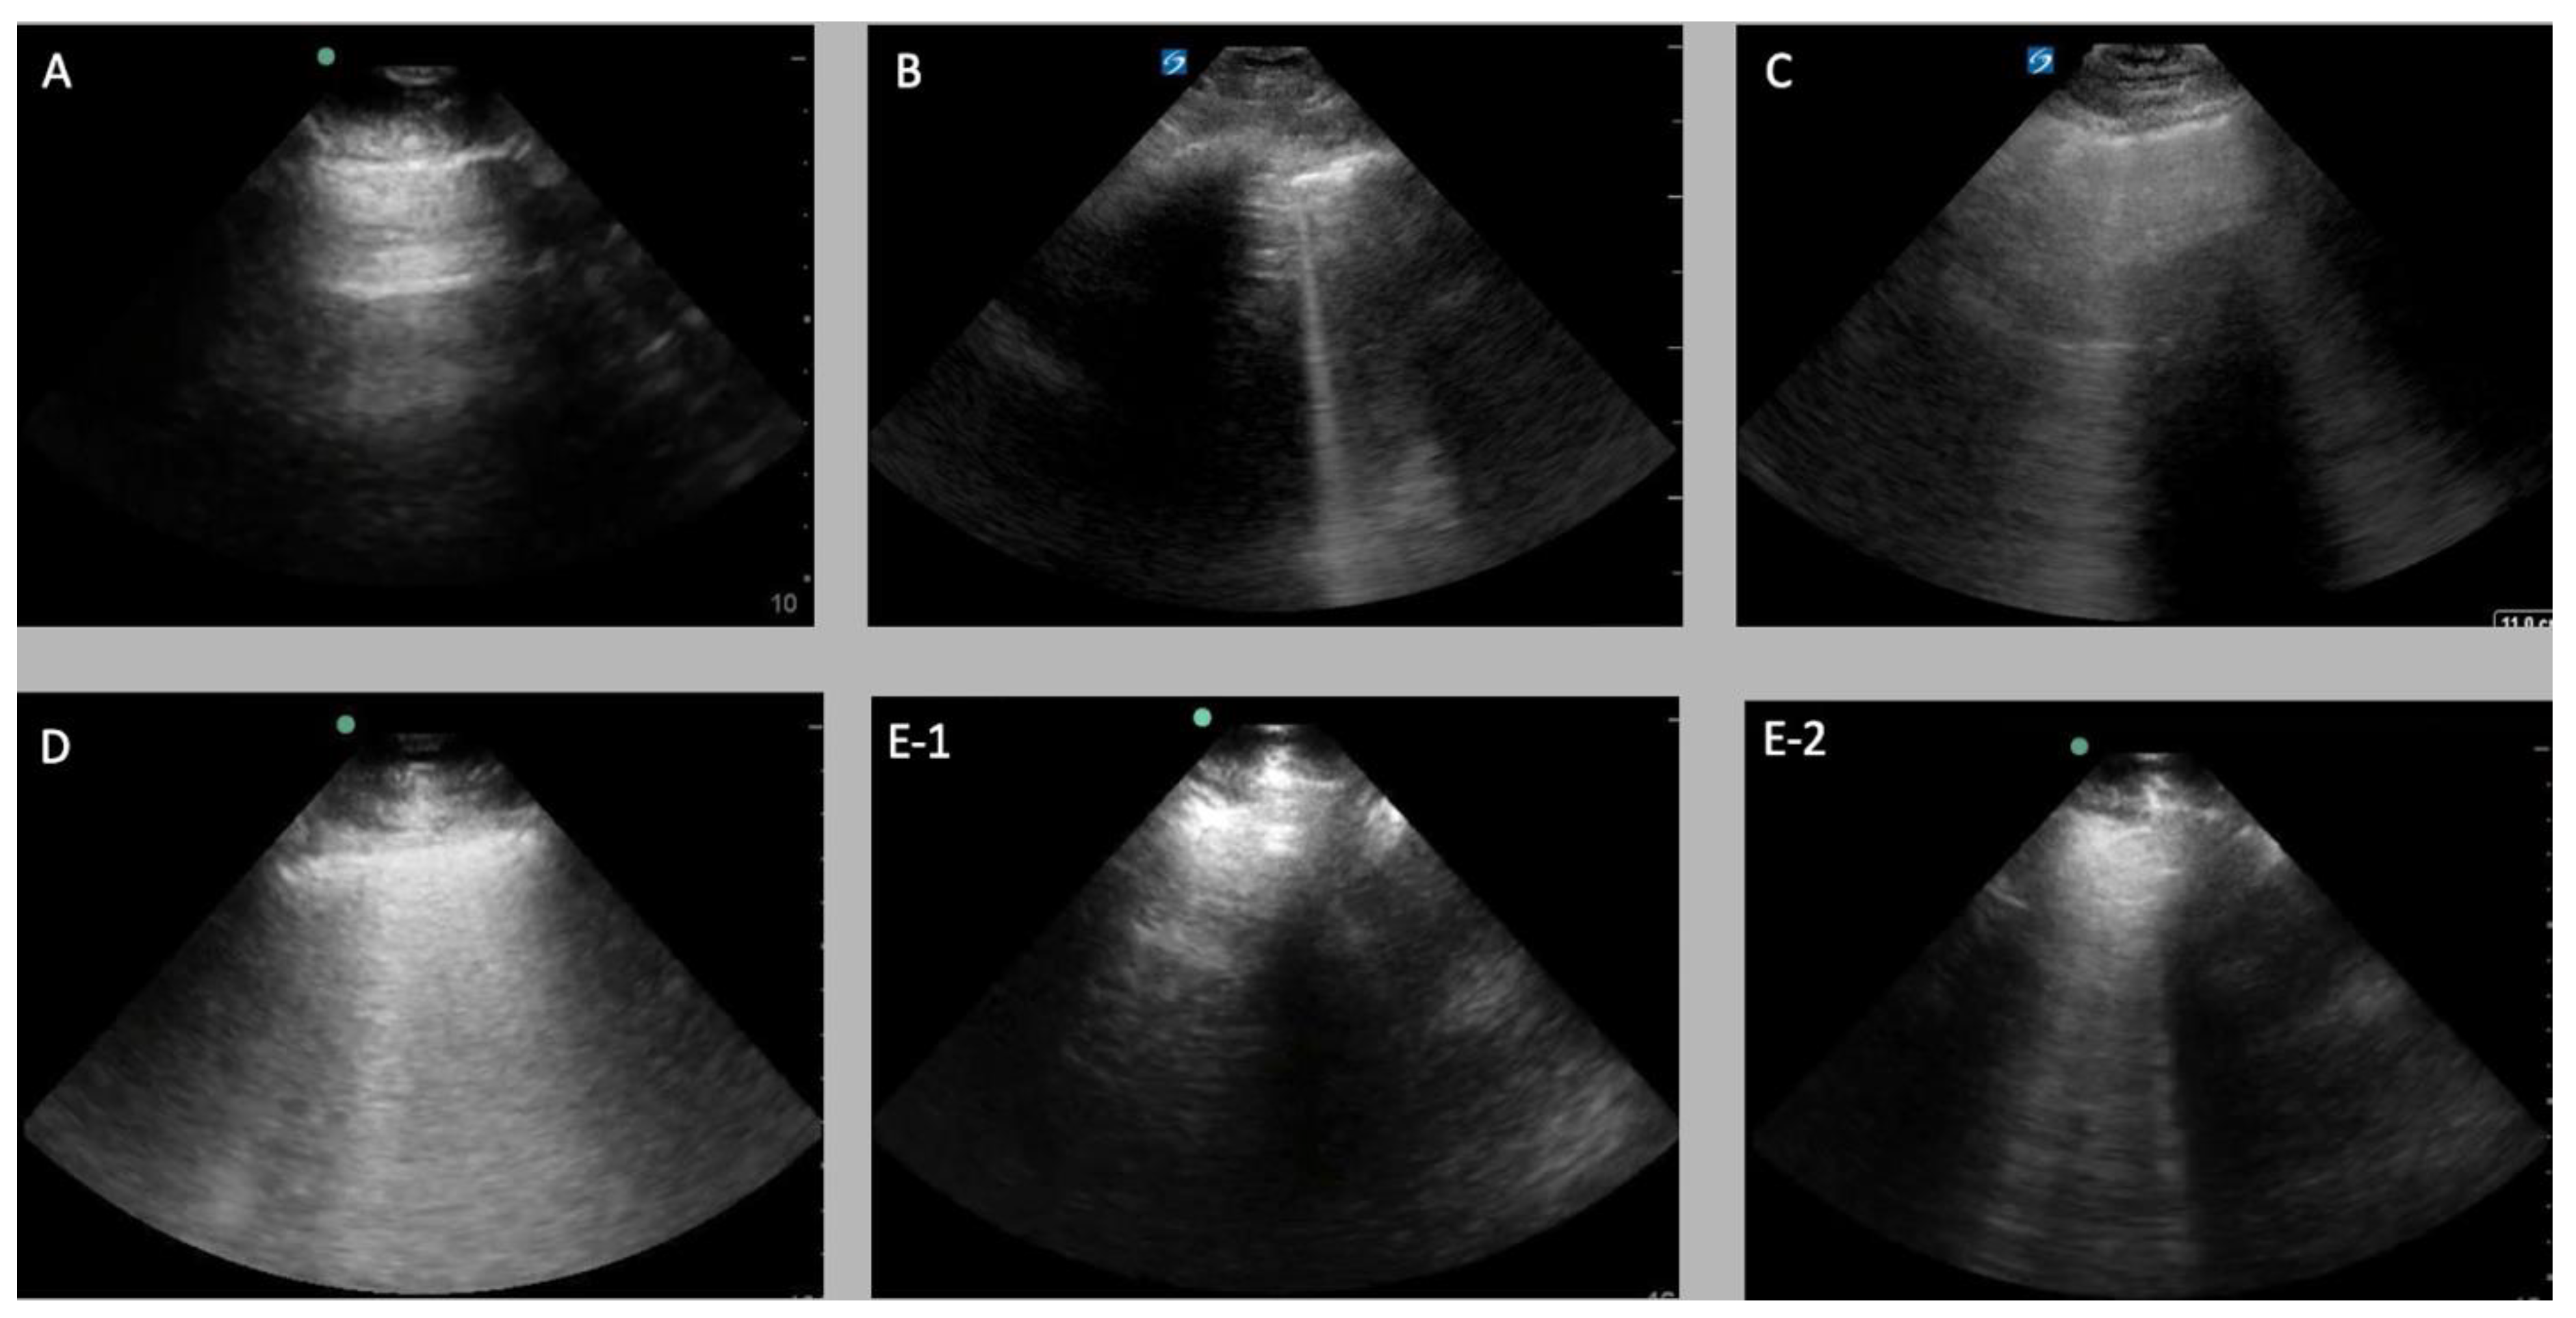

2.1.3. Data Labelling

2.2. Experimental Setup

2.2.1. Frame-Based Data

2.2.2. Clip-Based Inference Data